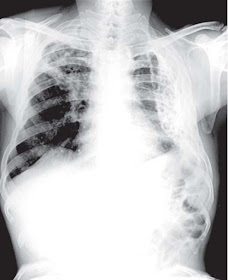

A 45 years old patient presents with history of cough and expectoration for several months. His chest X ray is shown below:

Describe the findings on the X ray and what could be the diagnosis?

X-ray chest shows that the lungs are large in volume with streaky shadows and multiple cystic lesions with air fluid levels. These cystic lesions can also be seen through the heart shadow. This is most probably a case of bronchiectasis.